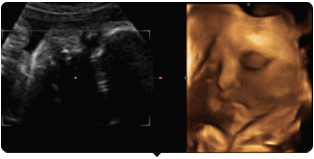

四维彩超就是四维成像技术(4D),能直观,立体显示人体器官的三维结构及动态、实时地观察立体结构。主要可以进行胎龄检测、分析胎儿的发育情况、筛查胎儿畸形等。

单胎为怀孕第20—28周,双胞胎为18-22周。因为这个时期的胎儿大小适中,羊水量充足,比较容易采集到相对清晰的图像。

四维彩超动图欣赏

麻麻,我在咬手指哟!